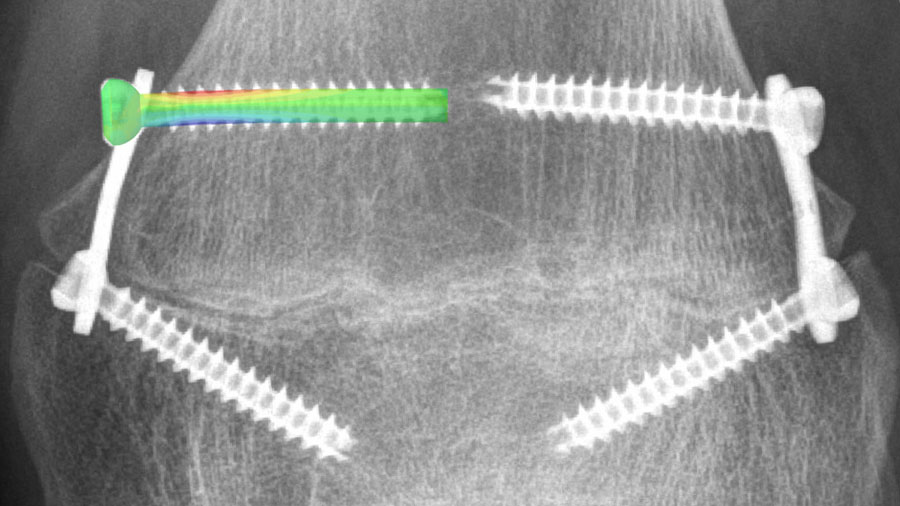

Biphasic Plate: New generation of locked plating

Healing complications occur in up to 10 percent of cases, of which a significant portion may be attributed to unfavorable mechanical conditions at the fracture. Moreover, state-of-the-art plates are prone to failure from excessive loading or fatigue.

A new biphasic plating concept has been developed to create controlled mechanical conditions for timely and robust bone healing and simultaneously improve implant strength. Thereby, the concept aims to enable confident early weight-bearing believed to be crucial for superior fracture repair.